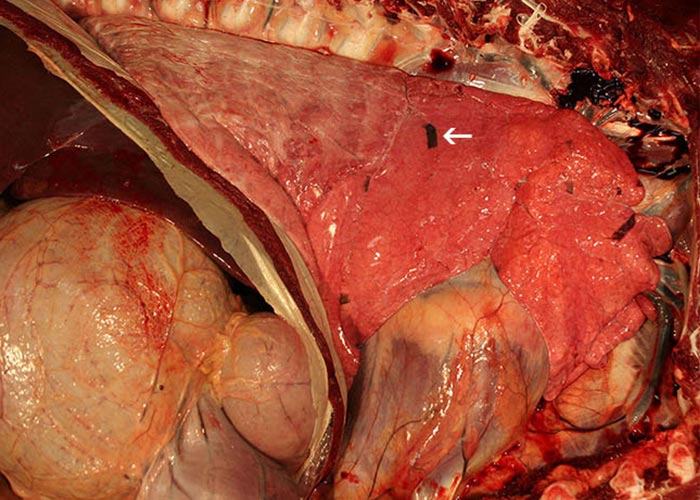

The lesions of MCF comprise a triad (Figures 18 a-c), involving multiple organ systems. The three components are vasculitis with lesions in medium and small calibre arteries and veins; inflammation of mucosal epithelia, particularly in digestive, respiratory and urogenital tracts; and lymphoid proliferation with subtle cytological atypia in lymph nodes and at sites of inflammation. It is useful for diagnosticians to remember this when they suspect MCF in an unfamiliar species (e.g. exotic ungulates) or a species not previously documented to have the disease. The distribution and severity of lesions in a given species tends to be consistent. For example, in cattle arteritis-phlebitis is usually florid and generalized, lymph nodes changes are moderate to marked, and digestive tract lesions are extensive and florid. In bison by contrast acute MCF is characterized by more modest arteritis-phlebitis, intestinal lesions largely limited to caecum and colon, and a more subtle generalized lymphadenopathy than that seen in cattle (Figure 19). In many cervid species, lymphadenopathy may be marked and associated with perinodal oedema. Marked lymphoid infiltration in kidneys often results in multifocal, grossly evident white foci in the cortex (Figures 20 and 21).140

Figure 18 a-c Triad inflammation in a bison with acute MCF. Mucosal inflammation with apoptosis (a – oesophagus); vasculitis (b - carotid rete artery) and lymphoid hyperplasia resulting in lymphadenopathy (c – lymph node) (Courtesy of D O’Toole, Department of Veterinary Sciences, 1174 Snowy Range Road, Laramie, Wyoming, USA, 82070)

Figure 19 Severe enlargement and congestion of the prescapular lymph node in a bovine (Courtesy of the Department of Veterinary Tropical Diseases, Faculty of Veterinary Science, University of Pretoria, Private Bag X04, Onderstepoort, Gauteng, South Africa, 0081)

Figure 27 Preclinical lesions of MCF in experimentally-infected bison. The small dark lobular areas of bronchointerstitial pneumonia (arrow) generally resolve by the time animals die in extremis or are euthanized. (Courtesy of D O’Toole, Department of Veterinary Sciences, 1174 Snowy Range Road, Laramie, Wyoming, USA, 82070)